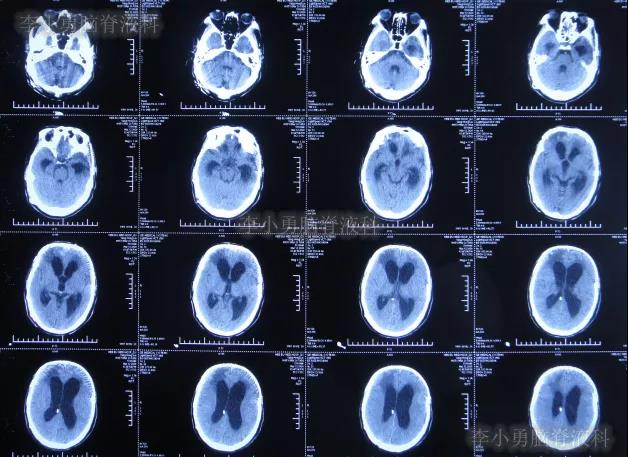

在第4家医院治疗26天,仍间断性发热、大小便失禁加重,住院期间曾2次查头颅CT(2020年2月27日(图-28)、2020年3月12日(图-29))示脑室仍扩张。

图-28:2020年2月27日头颅CT

图-29:2020年3月12日头颅CT

二、李小勇脑脊液科治疗过程和结果

2020年3月18日(颅脑外伤开颅术后149天即颅骨修补术后95天即第2次脑室腹腔分流术后62天,先后经4家医院治疗后仍意识模糊,大小便失禁,脑积水,间断发热近2月)转住入李小勇脑脊液科。入院时:意识模糊,大小便失禁,体重较前明显减轻,体温高38度左右;头部可见引流管走向;右侧肢体活动差些;鼻饲流食(图-30);入院时头颅CT示颅骨修补术后、脑室引流术后仍脑积水,有水肿(图-31)。

图-31:2020年3月18日头颅CT